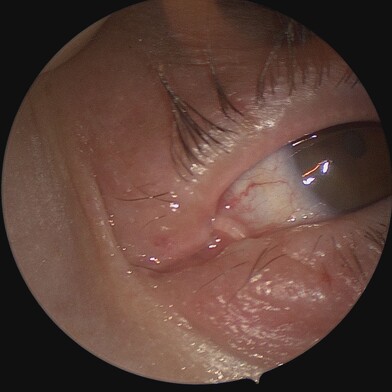

The endoscope is inserted through the nasal cavity to visualise and access the lacrimal sac and nasal bones. The bone is drilled away endoscopically, and a similar new pathway is created without external incisions. A mucosal flap is created to line the new passage connecting the lacrimal sac to the nasal cavity, ensuring proper drainage of tears. Silicone tubes or stents may be placed temporarily to keep the new pathway open and aid in healing.

The method is usually performed as an outpatient procedure, allowing patients to return home the same day. Patients may experience mild discomfort, swelling, or bruising around the eyes and nose, which can be managed with pain relievers and cold compresses. If silicone tubes are placed, they are usually removed after several weeks to months, depending on healing progress. Regular follow-up visits are also scheduled.